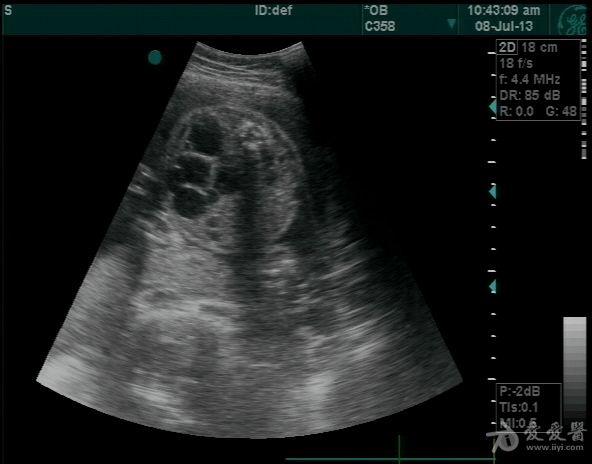

一组婴儿型多囊肾图像加引产后图片

图片尺寸802x602

图片尺寸799x599